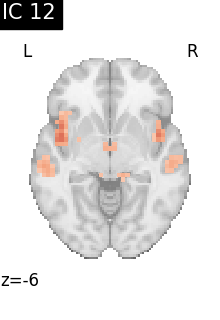

Finally, we plot the map for each ICA component separately

from nilearn.image import iter_img

from nilearn.plotting import plot_stat_map, show

for i, cur_img in enumerate(iter_img(canica_components_img)):

plot_stat_map(

cur_img,

display_mode="z",

title=f"IC {int(i)}",

cut_coords=1,

vmax=0.05,

vmin=-0.05,

colorbar=False,

)

show()